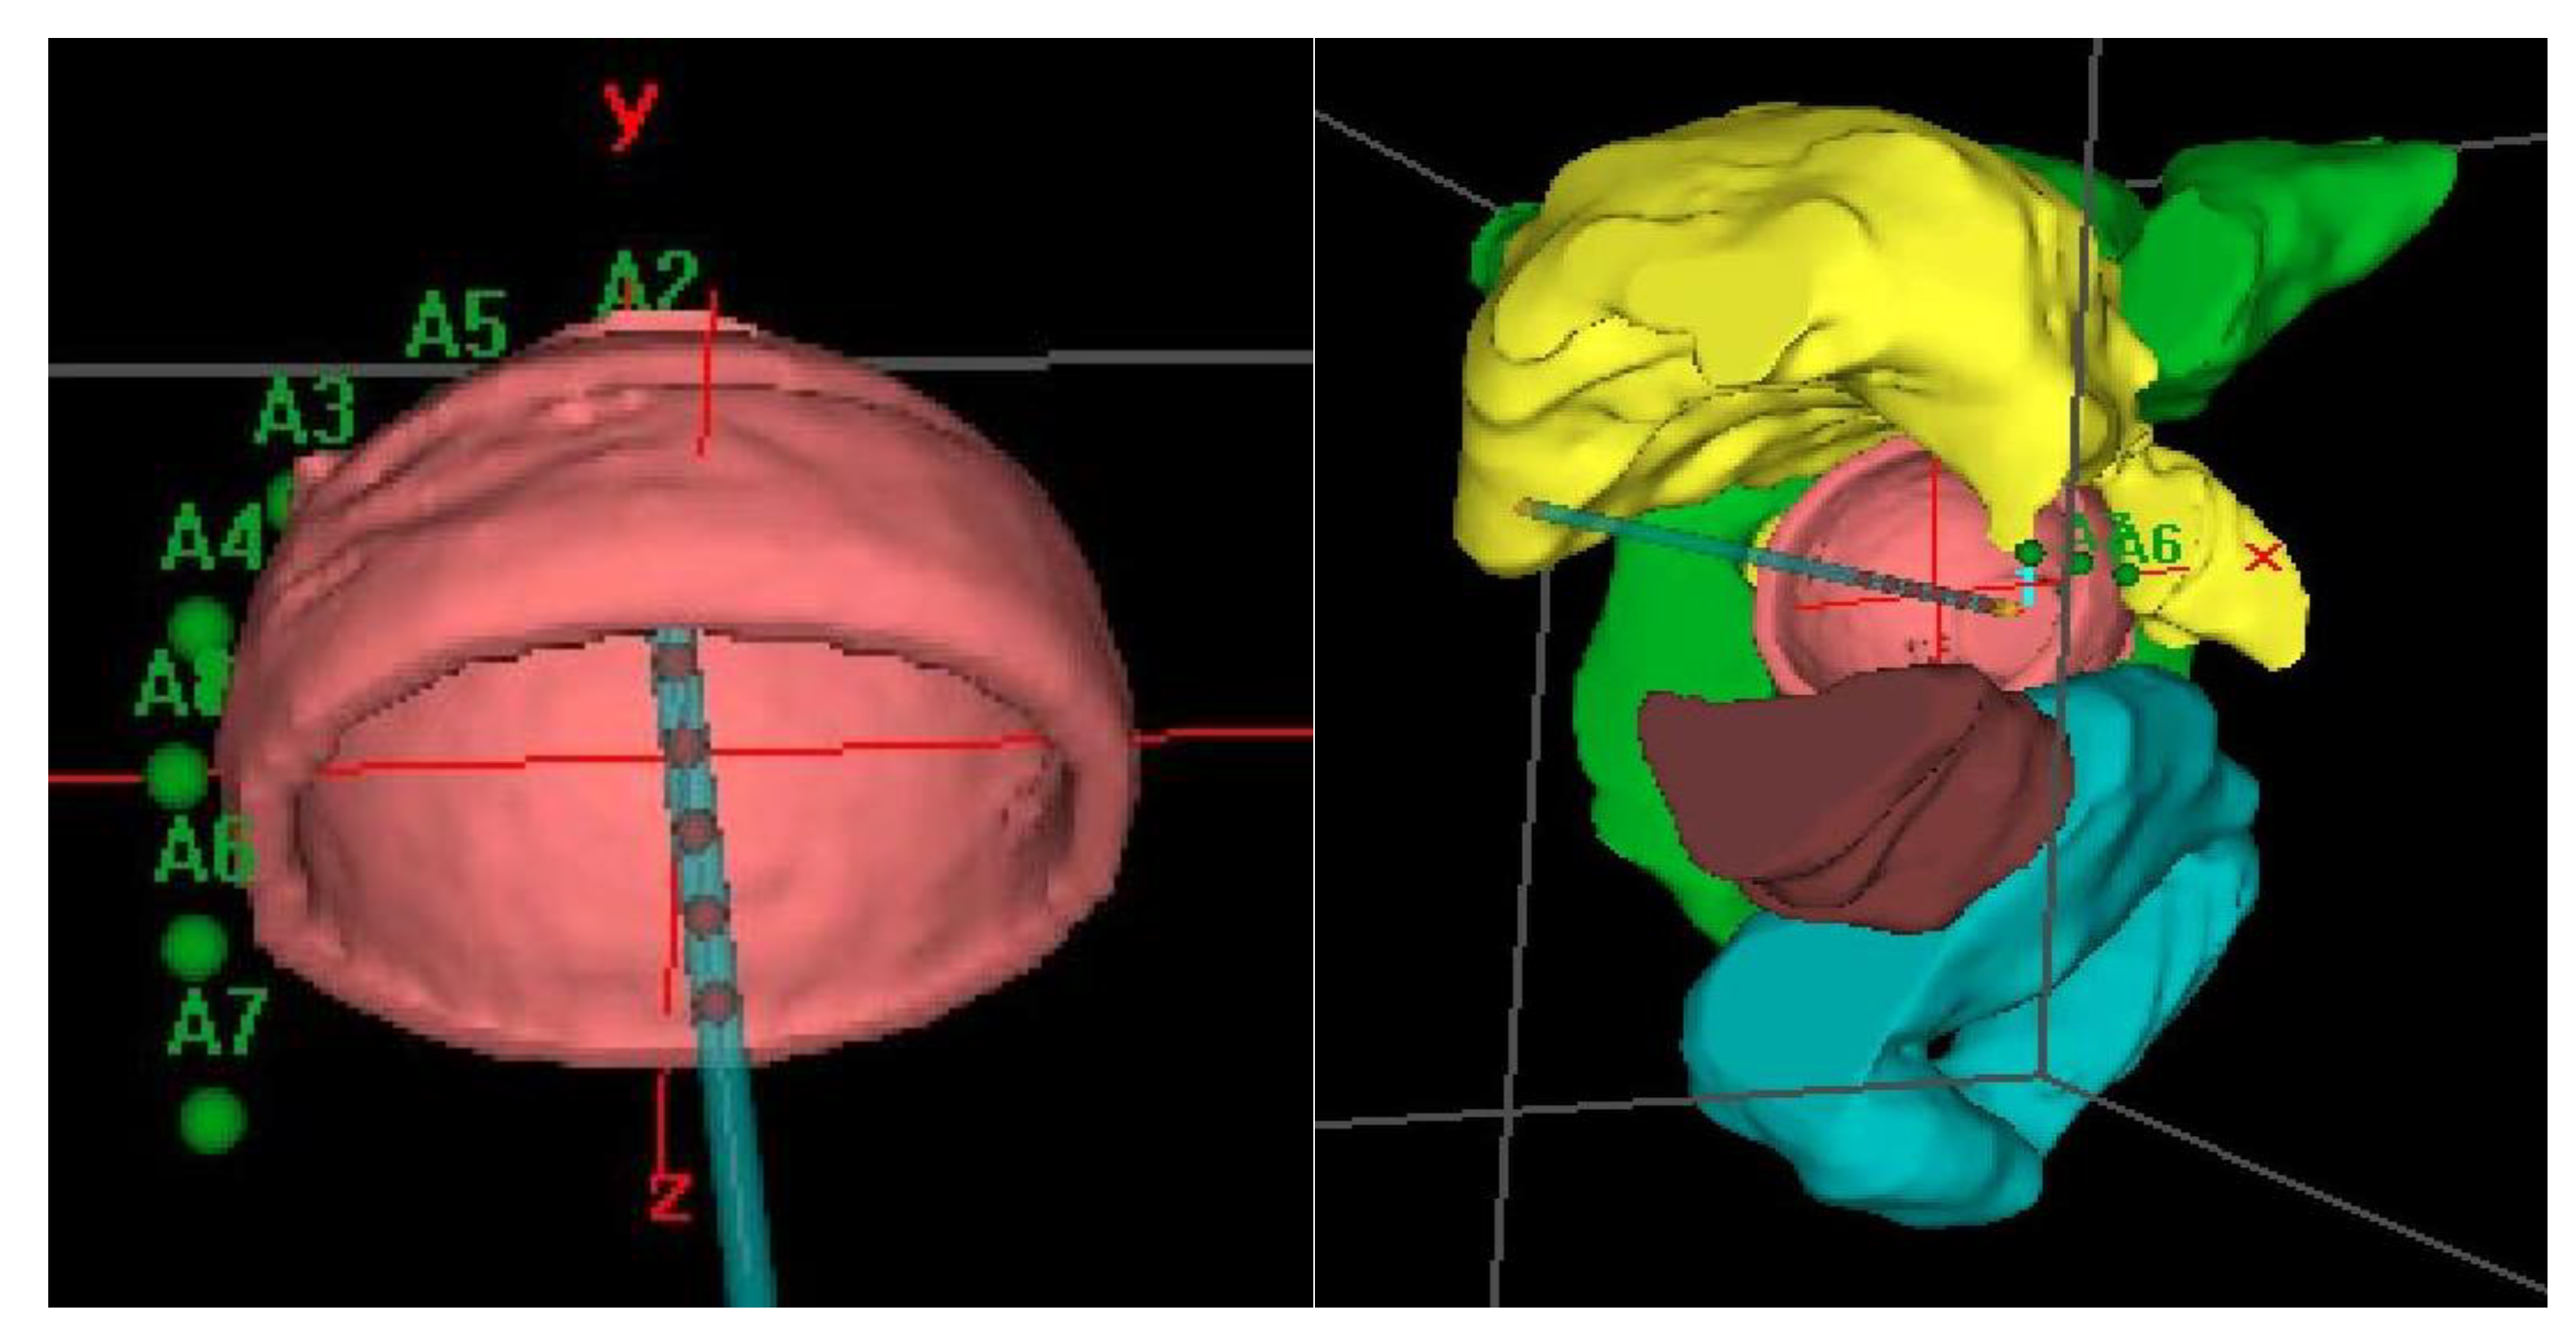

Prior to treatment, a computerized tomography (CT) simulation scan was performed with image acquisition every 1 mm for 3D planning. Special care was taken to confirm close contact of the applicator to the vagina in the CT in order to avoid relapses. Our procedure for clinical target volume (CTV) delineation consists of generating an automatic contour based on the difference in Hounsfield units of the applicator and the patient’s tissues. From this automatic contour, we generate an isotropic 3 mm margin, that is, the expansion volume. Then, a boolean subtraction of the applicator from the expansion volume is made. Finally, manual delineation of the external part of this volume is performed to adapt it to the real thickness of the vagina, which can vary depending on the case and cylinder diameter. For manual delineation, a 2 mm diameter pearl tool is used. The CTV was delineated along the first cylinder and the mean length of the postoperative treated vaginal cuff was 3cm; the rectum, bladder, and sigma were also delineated along 2 cm from the top to 2 cm under the CTV using the Oncentra Brachy planning system (V.4.5.3) (Elekta®,Nucletron BV, Veenendaal, The Netherlands). (Figure 2).

The dose was prescribed at a depth of 5 mm from the applicator surface, and point dose optimization based on distance was used. The active treatment length was 2.5 cm. In the present study, 90% of the isodose surface included the CTV. The voxels corresponding to the vaginal D2cc are always located in a small volume at the top of the vaginal-cuff and any reduction in the dose at this level will consequently reduce the dose at the prescription point. This 2cc volume is described and presented in Figure 3.

Distension of the rectum and air gaps have no impact on the D2cc of vagina considering that the 90% isodose always includes the CTV. The minimum dose of 90% received by 90% of the hottest CTV volume (D90) and the percentage of CTV coverage were calculated as well as the dose to the most exposed 2 cm3 of the rectum, bladder, and vagina. An EQD2(α/β = 3Gy) constraint of 65Gy for rectum and 80Gy for bladder were applied but were never necessary. Dose distribution was not modified to exclude the organs at risk from the dose prescription area. Figure 2 shows the dosimetric study with the area of the vagina most exposed to the dose. After dosimetric evaluation patients underwent treatment with an HDR microSelectron v2 Iridium 192 source and an afterloading source projector (Nucletron® microSelectron V3 digital ELEKTA, Holland, The Netherlands).

Figure 3. Example of dosimetric study showing the most exposed 2 cm3 of vagina to the dose in coronal (a), sagittal (b) and axial (c) planes and (d) dose volume histogram.